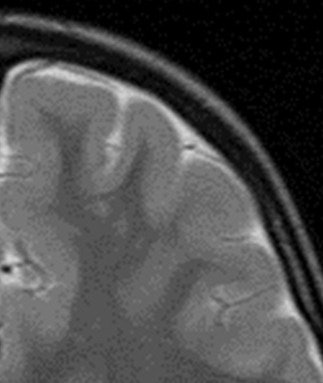

"The signal doesn't need to be abnormal," Ertl-Wagner explained. "With polymicrogyria, for example, where there are too many too small gyri, you usually have a normal signal but an abnormal gray matter-white matter junction."

Four basic sequences will answer most of the questions aimed at ruling out common malformations in children with developmental delay, Ertl-Wagner told delegates. These are T2-weighted axial sequence, T2-weighted sagittal sequence, FLAIR sequences, and T1-weighted inversion-recovery sequences. Motion correction sequences can be especially helpful when imaging children. In addition, 3D sequences can aid in detecting small abnormalities, in patients with epilepsy, for example.

The root cause of epilepsy can be very challenging to diagnose as often the abnormalities causing it can be very small, according to Ertl-Wagner. Some of the tiny focal cortical dysplasias with very small signal abnormalities are hard to visualize, and hard to pick up in images of the entire brain, she added.

Here diagnosis requires high resolution, preferably with a very good 3-tesla MR scanner, and optimized sequences, including 3D sequences, such as 3D FLAIR and 3D T1, and then for radiologists to really look for the focus, because finding it or not carries important therapeutic consequences for the patient.